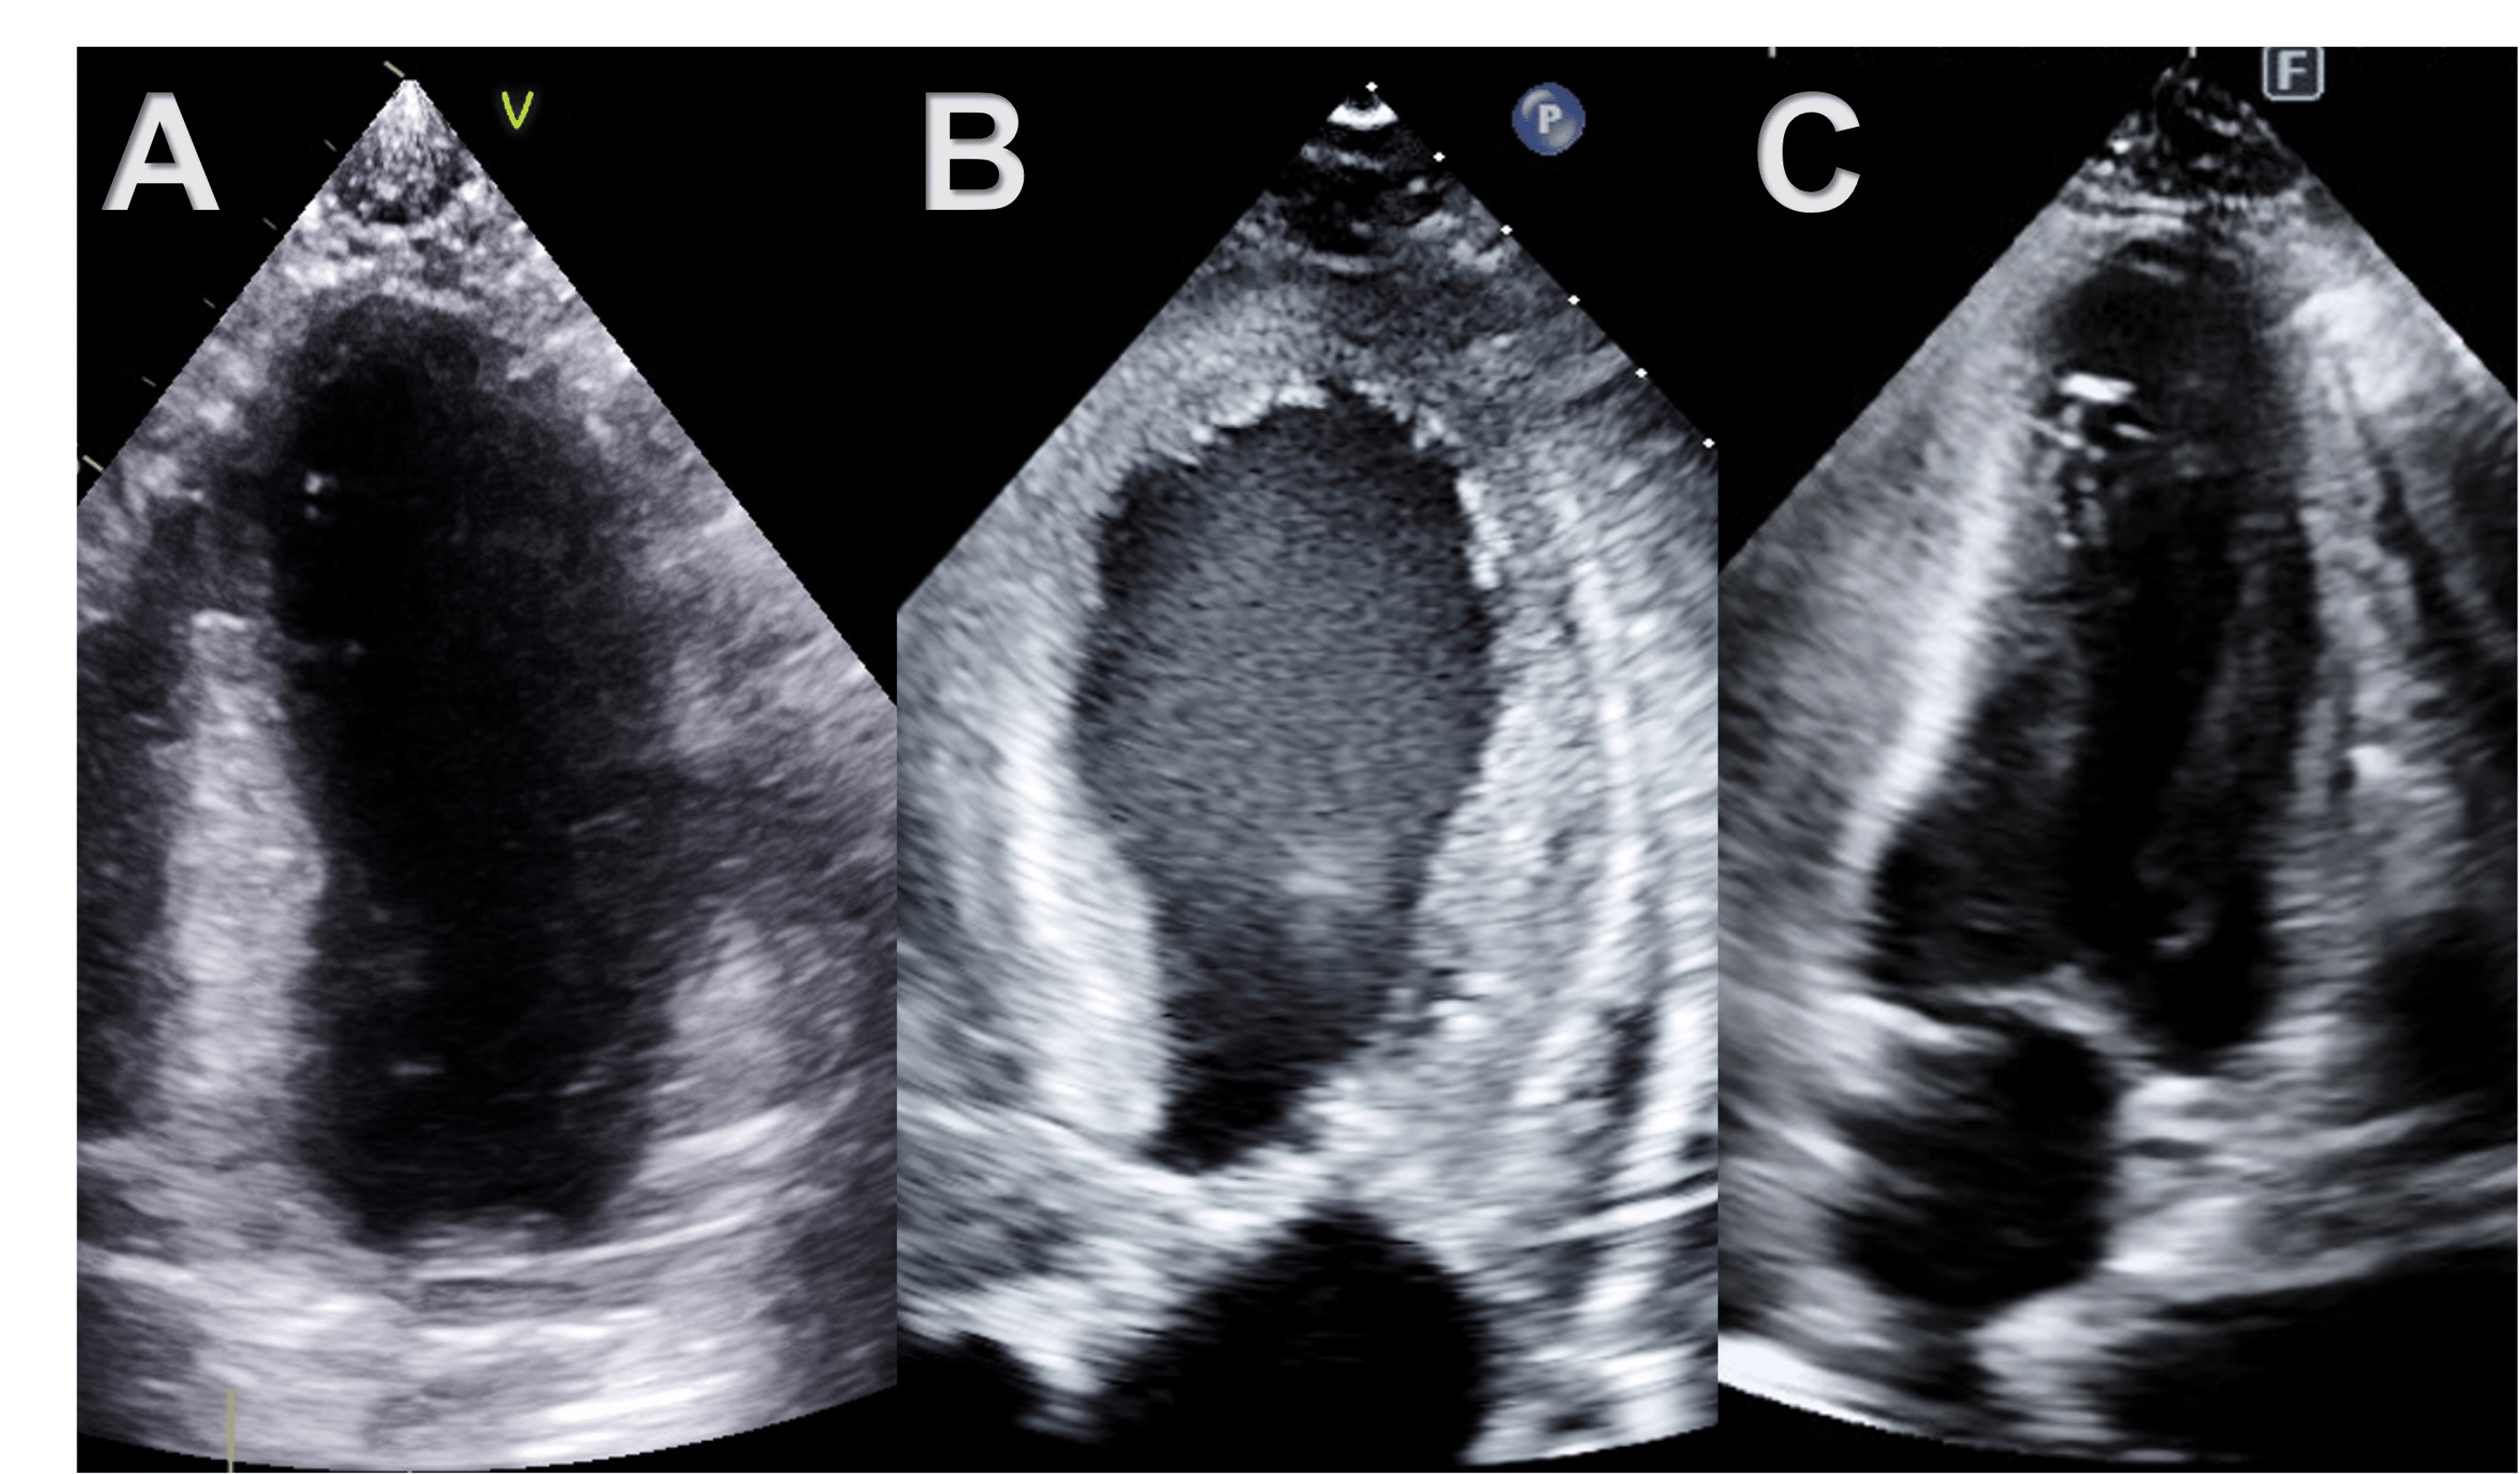

Initial echocardiography showing apical ballooning at diastole (A) and Apical Ballooning Echo Takotsubo cardiomyopathy—also called stress cardiomyopathy, apical ballooning syndrome, or broken heart syndrome—is a. There is a systolic apical ballooning of the left ventricle, with depressed mid and apical segments, and also hyperkinesis of the basal walls. In summary, the available pathophysiological information indicates that the apical ballooning that characterizes takotsubo cardiomyopathy reflects toxic. Ttc is originally described as apical ballooning. Apical Ballooning Echo.

Apical fourchamber transthoracic echocardiography view during (A Apical Ballooning Echo In summary, the available pathophysiological information indicates that the apical ballooning that characterizes takotsubo cardiomyopathy reflects toxic. This risk varies depending on disease severity. Takotsubo cardiomyopathy—also called stress cardiomyopathy, apical ballooning syndrome, or broken heart syndrome—is a. Ttc is originally described as apical ballooning due to apical (with or without midventricular segment) akinesis or. There is a systolic apical ballooning. Apical Ballooning Echo.